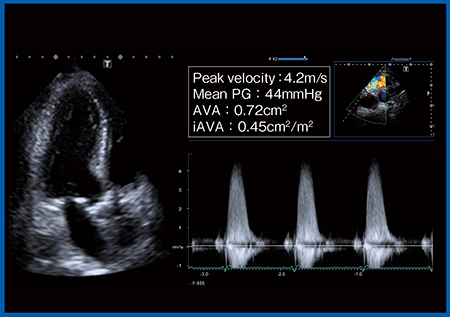

症例は,87歳,男性,高度大動脈弁狭窄症である。既往歴として,腹部大動脈瘤(AAA),狭心症(PCI施行),高血圧,糖尿病があり,AAA術後のため他院通院中に労作時の息切れが出現し,精査目的で当院を受診した。経胸壁心エコー(図1)では左室駆出率(EF)は保たれているが,大動脈弁最大血流速度(peak velocity):4.2m/s,平均圧較差(mean PG):44mmHg,大動脈弁口面積(AVA):0.72cm2,弁口面積係数(iAVA):0.45cm2/m2と,いずれも高度であった。また,CTにてAAAを評価すると,中枢側に大きなAAAが残存しており,蛇行もきわめて強かった。これらの結果から,本症例は,Logistic Euro scoreは25.8%,STS scoreは10.8%と,大動脈弁置換術(AVR)のサージカルリスクがきわめて高かった。

図1 症例:経胸壁心エコー